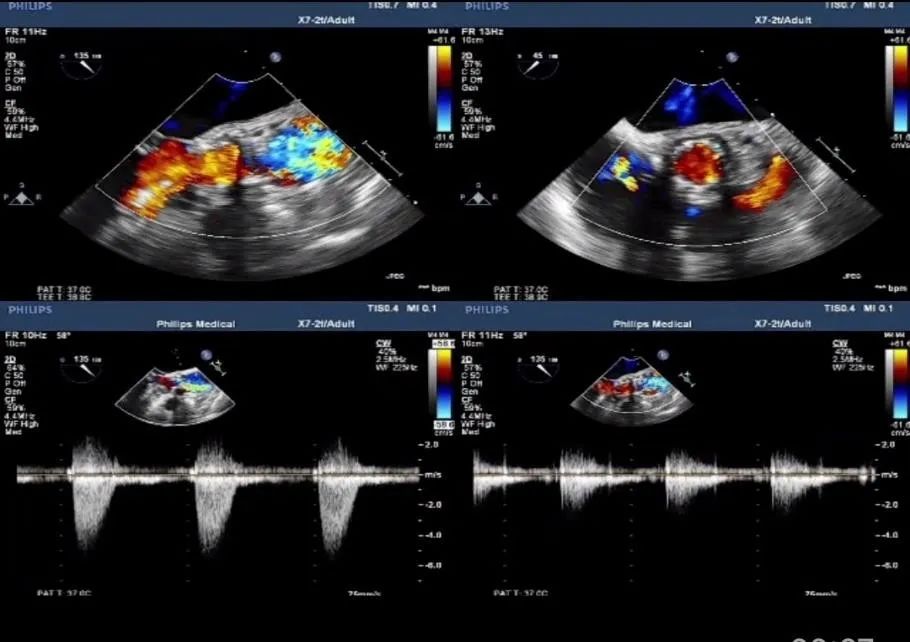

术后超声: